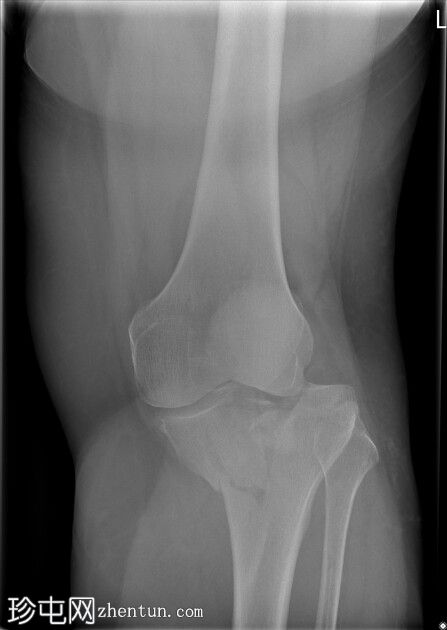

左膝X光片

X光片

正面

胫骨近端内侧骨折,伴有隆起处凹陷和外翻。

Schatzker IV型。左胫骨近端。